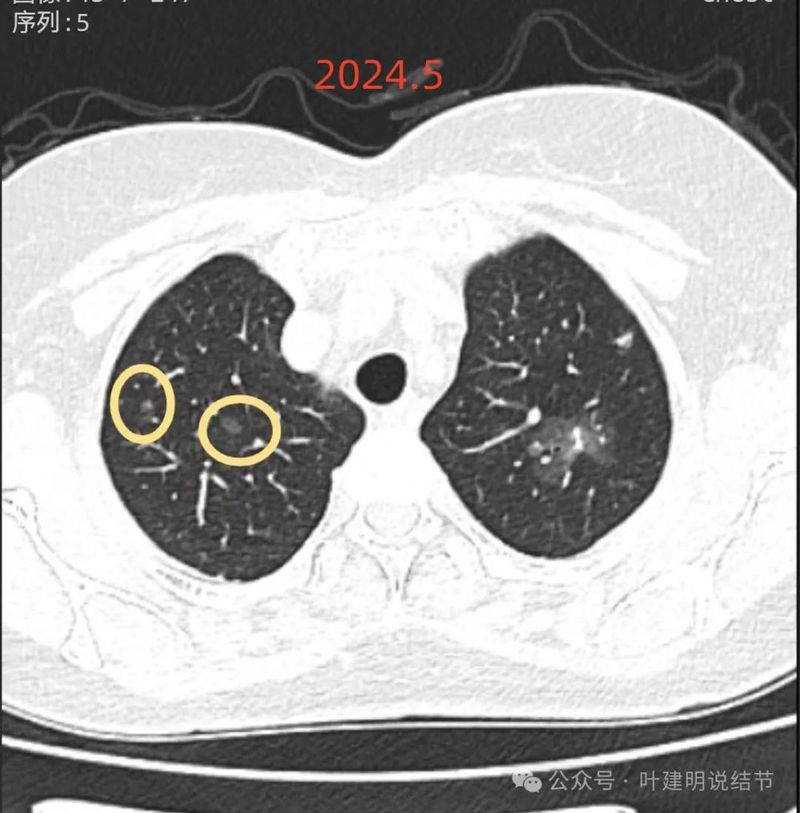

再看2024年5月时的影像:

病灶3:右上叶微小结节,磨玻璃密度,有微小血管穿行,不典型增生或原位癌可能性大;

病灶4:右上叶淡而轮廓与边界均清楚的磨玻璃结节,考虑不典型增生或肺泡上皮增生可能性大;

两肺多发磨玻璃结节,部分是混合密度。主病灶是红色这处在左上叶的,对比2021年有明显增大进展,考虑是浸润性腺癌可能性大,或者微浸润性腺癌;粉色的考虑原位癌可能性大;橘色的考虑不典型增生可能性大;黄色的考虑肺泡上皮增生可能性大;紫色的考虑微浸润性腺癌可能性大;绿色的考虑良性的可能性大;蓝色的考虑浸润性腺癌或者微浸润性腺癌;黑色的是2021年的时候比较明显的几处病灶。总体对比来看红色的范围增大比较明显,实性成分也有增加;蓝色的密度增加比较明显。首先考虑是多原发早期肺癌。个人觉得继续随访存在一定风险,当然由于病灶太多,也不是说都靠外科手术能够解决问题的,但是主要的有风险的病灶如果能够手术还是需要手术先解决,其他次要的病灶后续再考虑消融或者其他治疗。我的想法是先做右肺下叶背段切除(紫色,考虑微浸润或浸润)加上叶楔形切除(蓝色),下叶粉色的也可楔切或不切;之后看恢复情况过三个月左右再做左肺上叶切除。其余病灶后续如果随访进展考虑消融控制。意见供参考!为何先建议做右侧:先做右侧是因为右侧切得少,到时候再切左侧的时候,单肺通气更能耐受。如果先做左侧,下次做右侧时,左下叶单肺通气不太能耐受些。而且蓝色这处密度增加明显,又贴着胸膜,它的风险相对来说也较高,或许比左上红色的还高点。所以先做右侧。若非转移,靶向药个人不太建议吃,又不是晚期,是多原发早期肺癌可能性大呀。